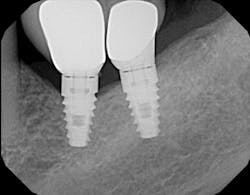

4. Mixing parts from different companies can cause component misfit. Third-party parts from “cheaper” implant companies may be used to lower cost, but they don’t always result in complete fit. In fact, implant companies that warranty their parts for replacement often void this warranty if those parts are used in combination with parts from another company (figure 3).